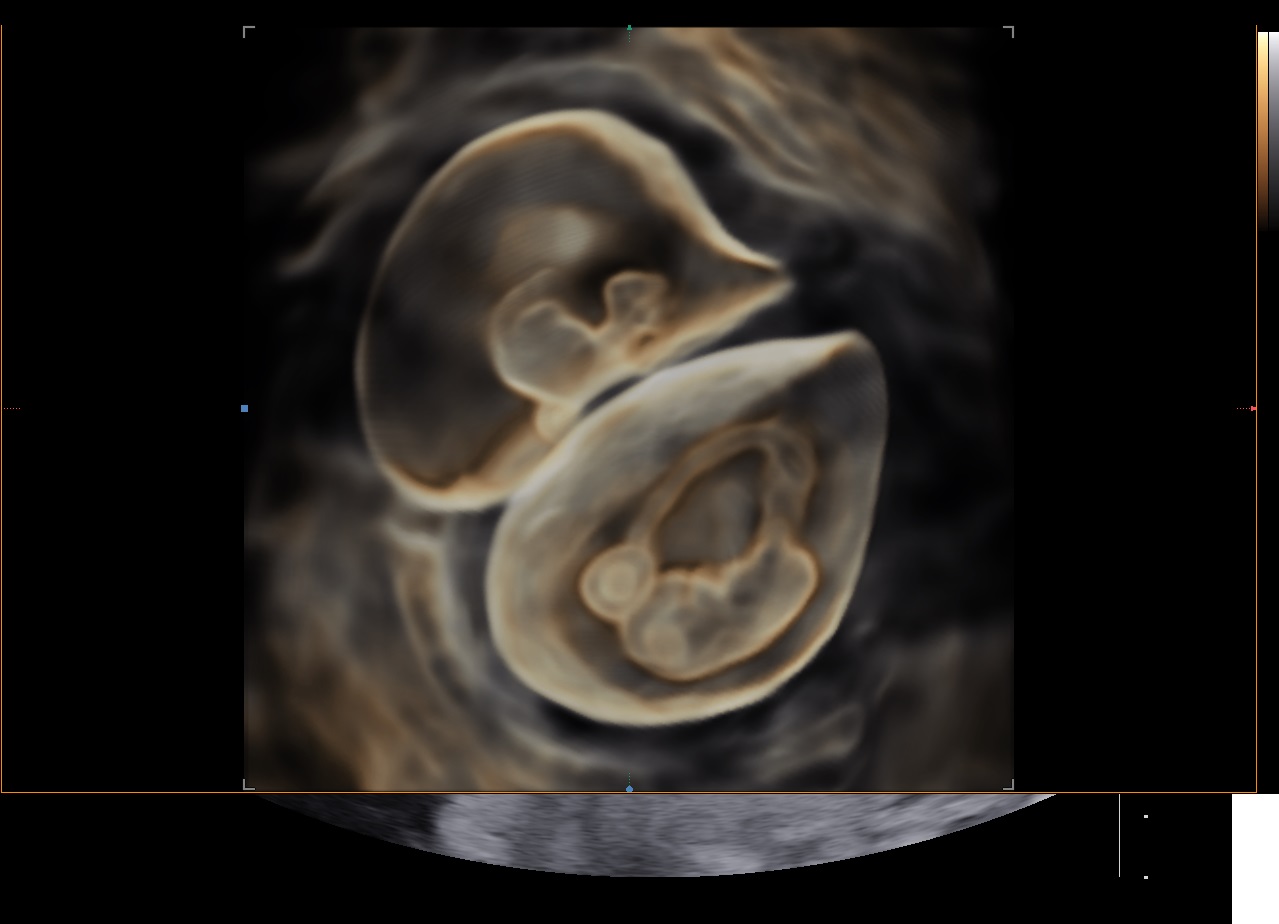

Le RealisticVue™ propose des rendus anatomiques de haute résolution en 3D/4D. Une source lumineuse est modélisée afin de permettre un effet d'ombre sur les structures et de surligner les zones d'intérêt.